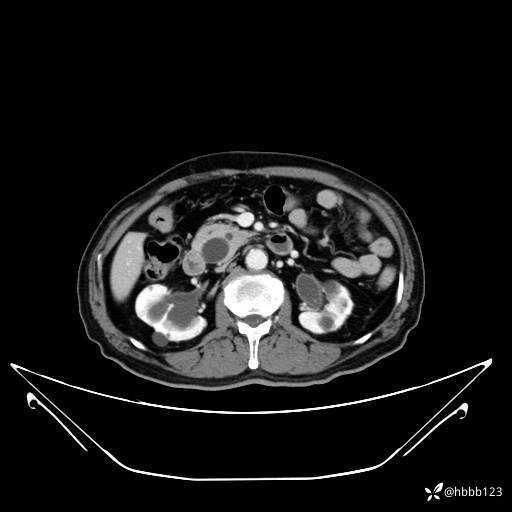

平扫: